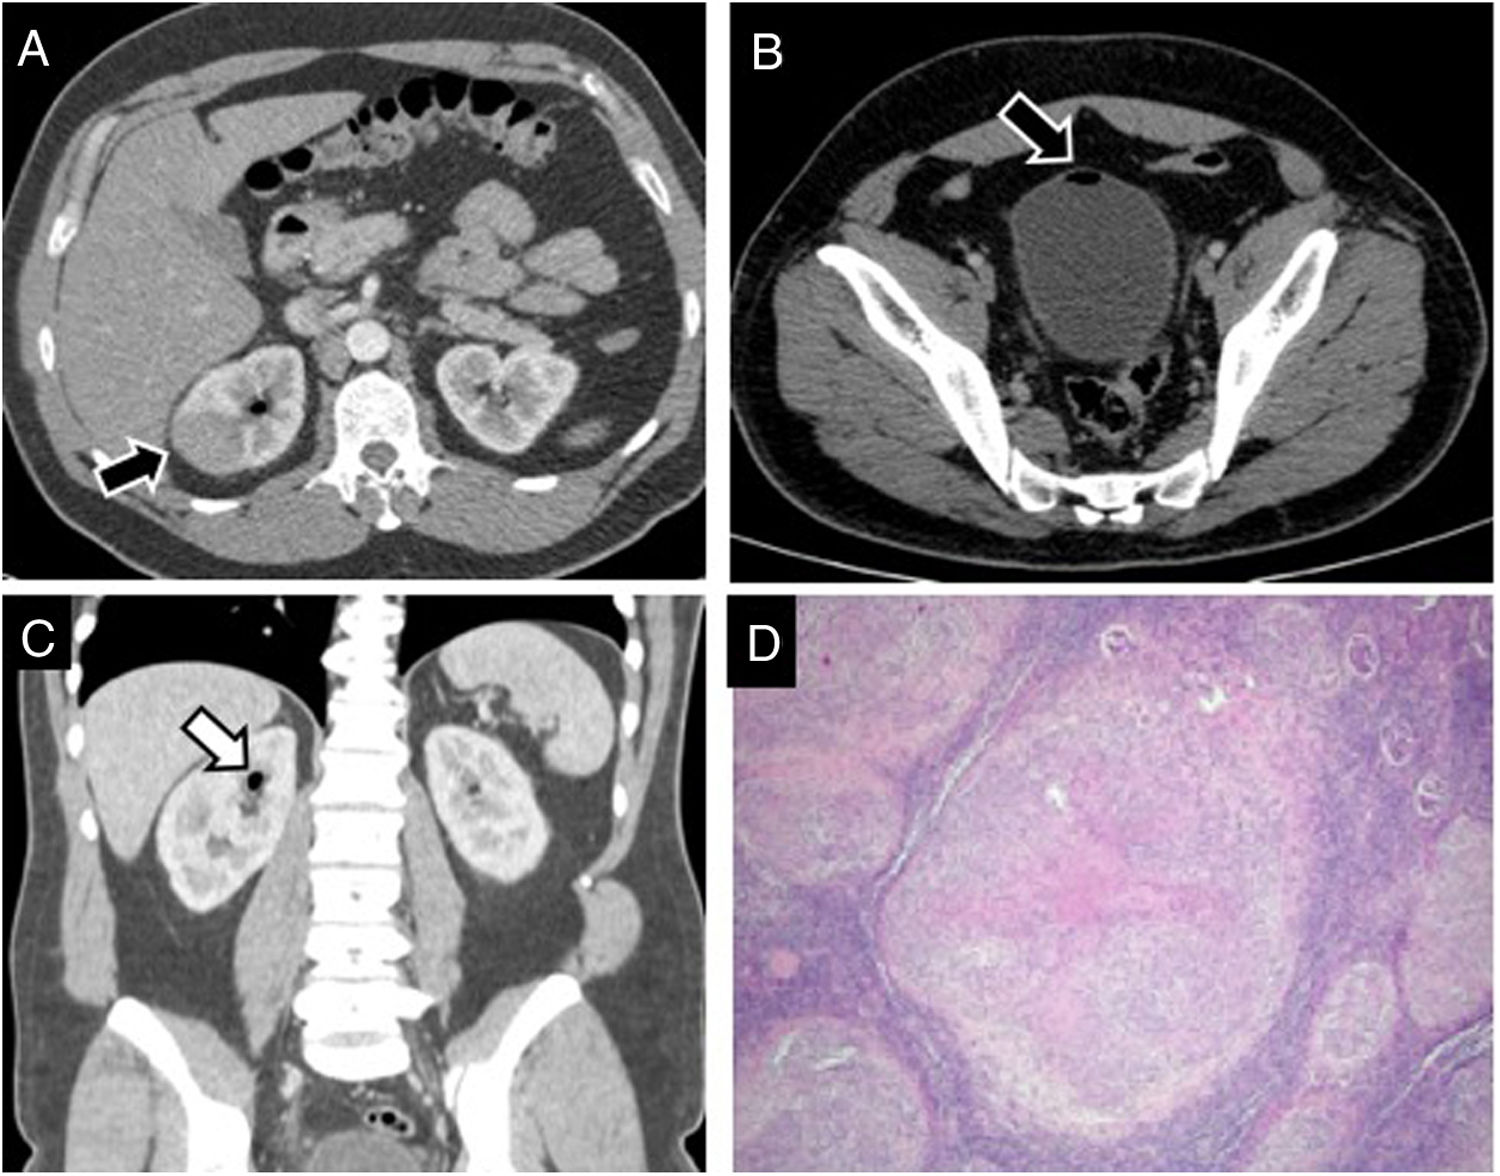

After TURBT, a routine follow-up CT was performed that showed a homogeneous solid mass in the right kidney upper pole (Fig. 1A–C), firstly diagnosed as a renal tumour, suspected to be a renal cell carcinoma.

A. Contrast-enhanced venous phase CT images (A, B axial; C, coronal view) show a hypoattenuated focal lesion (arrow) in the upper pole of the right kidney. B, C. Presence of gas into the bladder (arrow in B) and the superior collector system (arrow in C) is seen that presumes vesicoureteral reflux after transurethral resection. D. Low power examination of renal parenchyma revealing the presence of multiple nodular lesions throughout the whole specimen (hematoxylin and eosin staining, 4×).

The patient underwent partial nephrectomy obtaining tissue samples without malignant cells. Pathology examination demonstrated caseating and non-caseating granulomas (Fig. 1D).

A follow-up CT examination, performed eighteen months after TURBT, demonstrated a new hypoenhancing solid lesion similar to the initial mass and located in the right kidney upper pole near previous scar (Fig. 2). Relapsing of granulomatous affectation was suspected and patient was treated with rifampicin, isoniazid and ethambutol with a complete resolution on posterior imaging studies.

Renal complications after BCG include granulomatous affectation, abscesses, pyelonephritis and interstitial nephritis.3,4 BCG can reach the upper urinary tract by not completely understood mechanism. Hematogenous dissemination and/or direct seeding by vesicoureteral reflux are the proposed mechanisms.

Another mechanism by which the kidney is affected is vesicoureteral reflux, which explains the preference for affectation in the upper renal poles.3 According to previous reports, there is a preference for abscess and granuloma formation in the upper renal pole because they tend to be more affected by the reflux.3

Renal granulomas present in imaging as a single or multifocal solid masses, mimicking papillary renal cell carcinoma or parenchymal infiltration by transitional cell carcinoma.5 Renal ultrasound commonly shows an echogenic mass. On contrast-enhanced CT they appear as hypovascular mass compared to surrounding renal parenchyma.1,3 On MRI, they are characteristically hypo to isointense on T1WI with variable signal intensity on T2WI depending on the inflammation and fibrotic component. After contrast, they present low enhancement as on CT.3